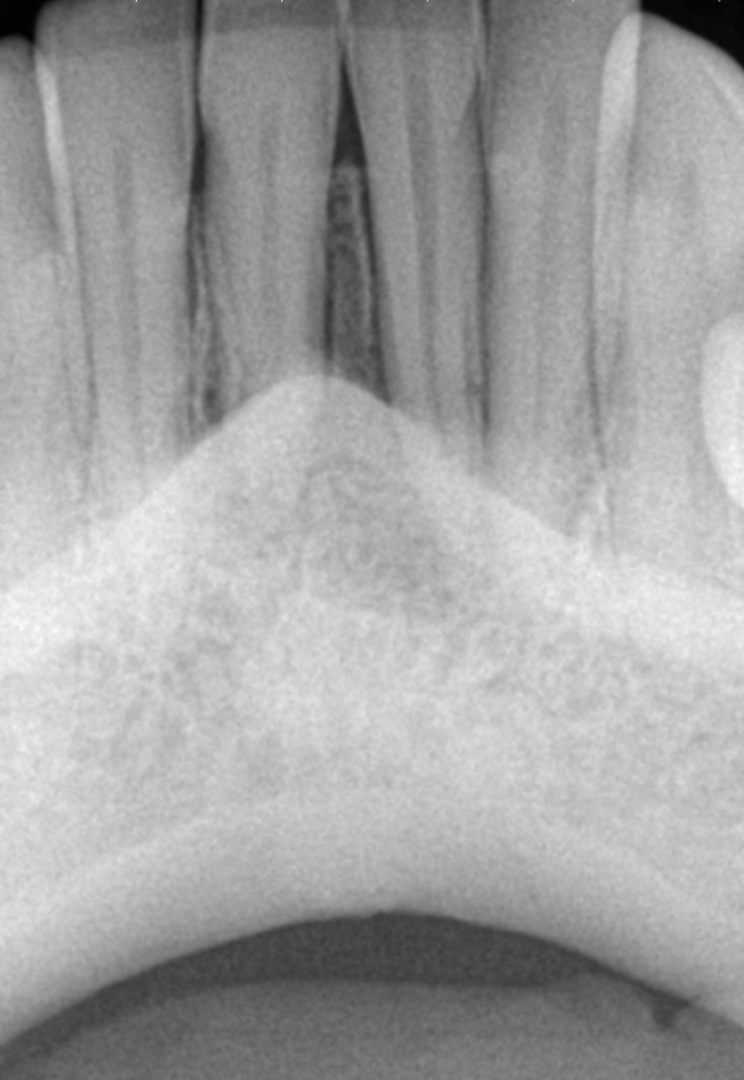

A radiograph was taken of the immediate postoperative situation and at the nine-month follow-up. Comparison showed bone apposition between the two central incisors (Fig. 4). An i-CAT scan was also taken at the nine-month follow-up to check the bone growth. The horizontal view, taken at the same level as that taken preoperatively, clearly showed the reduction of the gap from 14.11 mm to 4.42 mm at the cortical level and the trabecular bone showed the same trend in healing (Fig. 5). The vertical view showed that the bone on the buccal plate was growing towards the root and growing vertically (Fig. 6). Almost 8.2 mm in height had been regained and in direct contact with the roots of the teeth. Indeed, when provided with a scaffold on which to grow, the bone can grow in all directions, including vertically, where there was an open periodontal pocket. This is the major breakthrough of this technique. No bone grafting material or a membrane was placed. The periosteum was in great condition, and for me, it was the best membrane I could wish for.

Fig. 5a: Comparison of the horizontal views of the i-CAT scans taken pre-op ....

Fig. 5b: ...and at the nine-month follow-up.

A comparison of the i-CAT scans taken preoperatively and at the nine-month and 18 month follow-ups showed complete regeneration of the cortical and trabecular bone in great biological detail, showing even the groove of the frenum (Figs. 7 & 8). The bone view clearly showed the preoperative major horizontal and vertical bone defect and open periodontal defect, the beautifully regenerated, natural looking bone and the emergence of the mandibular nerve. Happily, the bone continued growing vertically (Fig. 9).